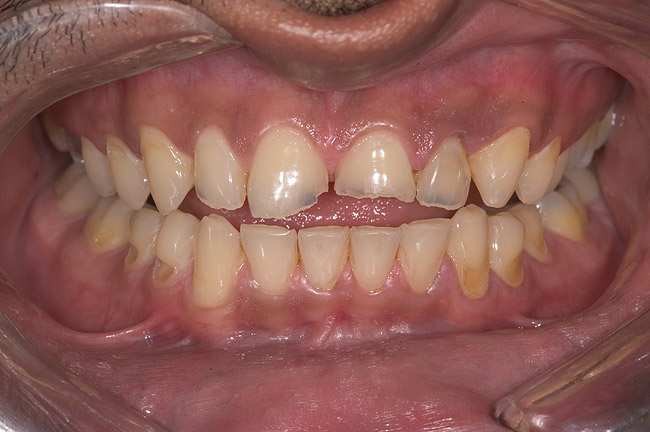

Figure 4  Preoperative smile view.

Figure 4

A 20-year-old male patient presented with irregular upper anterior teeth and was unhappy with his smile (Figure 4). He complained of occasional generalized mild sensitivity. Dental treatment history revealed that he had occasional dental work done in the past. Two weeks previously, he had severe pain in tooth No. 10, which was treated endodontically, and he was then referred to the author’s practice for management of anterior wear. Tooth No. 3 had a broken amalgam restoration.

Examination revealed that palatal surfaces of teeth Nos. 6 through 11 showed severe loss of tooth structure, with mild wear on the lower incisors and loss of anterior guidance (Figure 5 through Figure 7). The palatal TSL was consistent with the clinical picture presented by patients with gastric reflux. A detailed medical history was taken, and the patient complained of having heartburn and acidity at least 4 out of 7 days a week. He had never sought treatment for it and used over-the-counter medication when needed. He was a nonsmoker, with occasional intake of alcohol. He had a high-stress job with irregular meal times. A thorough smile and dental analysis11 was carried out; the findings appear in Table 2.